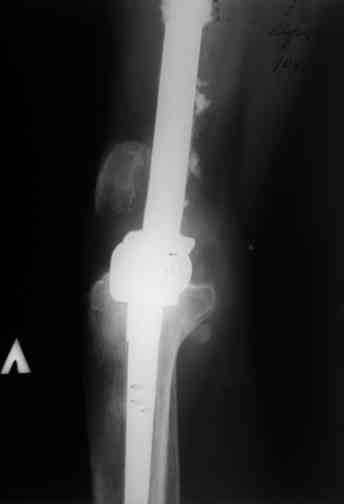

Прикрепляю пример замещения дефекта бедра 20 см, после резекции по поводу опухоли, эндопротеза Сиваша, вялотекущего остеомиелита со свищами в течении 3 лет. Получилось хорошо и всего за 6 месяцев в аппарате. Колена не было. У Вас случай сложнее. Это было в 1998г. Я работал в ЦИТО и у меня было 4 больных, я занимался им с утра до ночи. Сейчас 60 больных и операций в нашем отделении 25-30 в неделю.Если могу чем помочь - нет проблем.